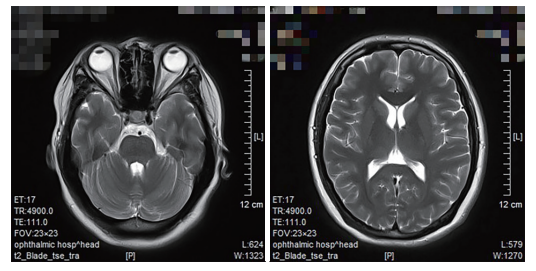

患者,女,31岁,因 “双眼视物不清 2 d” 于河北省眼科医院就诊。体格检查:双眼视力 1.0,右眼眼压 [非接触式眼压计 (non-contact tonometer,NCT)] 16 mmHg(1 mmHg=0.133 kPa),左眼眼压 17 mmHg,双眼外眼检查未见异常,瞳孔散大,直径约 8 mm,直、间接对光反射及近反射均消失,余前后节检查未见明显异常(图 1)。神经查体:膝腱和跟腱反射均消失。既往体健,否认服用药物,无外伤及手术史。辅助检查:梅毒抗体阴性。头颅 MRI:未见明显异常(图 2)。药物试验:用稀释后的毛果芸香碱滴眼液(浓度为 0.0625%)滴双眼,约 30 min 后患者双侧瞳孔缩小至 3 mm(图 3)。

图2 头颅MRI未见明显异常

Figure 2 Head MRI shows no obvious abnormality